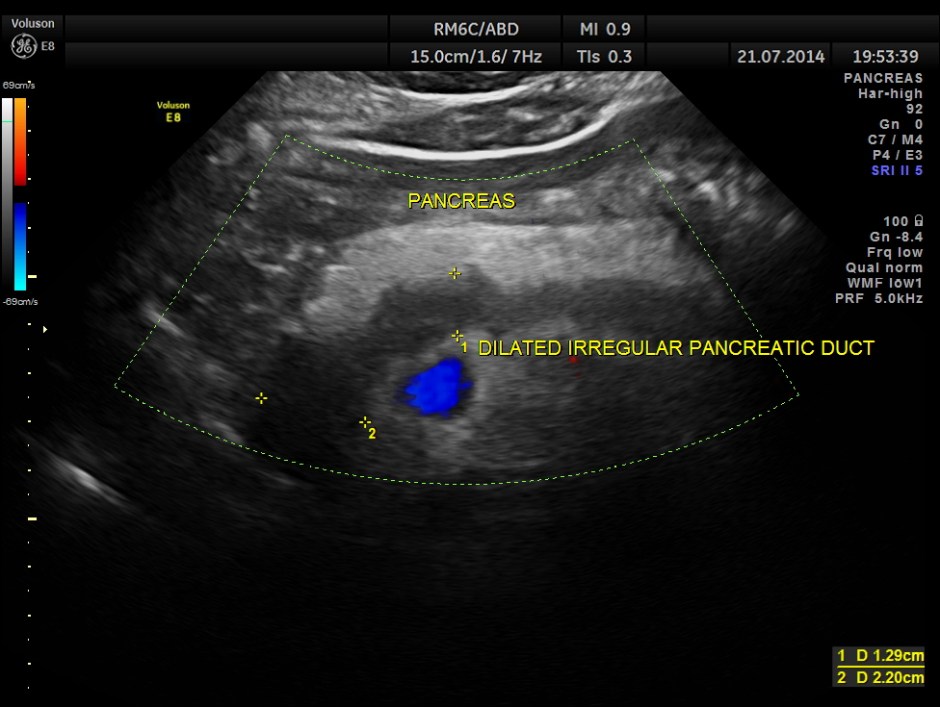

The following pictures show the pancreas.

Pancreatic duct is dilated prominently.

Pancreatic duct dilated.- 12.9 mms.

Pancreatic calculi are seen.